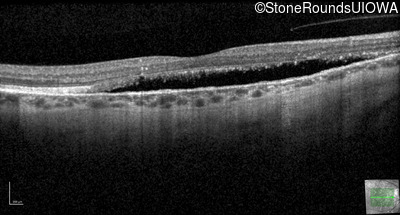

Optical Coherence Tomography - Right - 20/25 +2 sc

Exemplar / OCT Stack